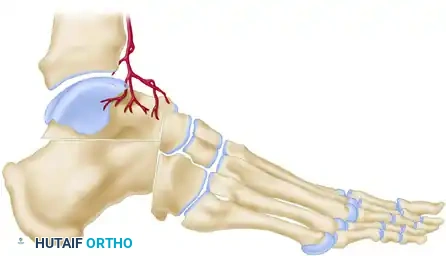

Step 6: Calcaneal Fixation

Pass the tendon deep to the peroneus longus tendon. The graft must now be secured to the lateral wall of the calcaneus to recreate the calcaneofibular ligament (CFL).

Drill a pilot hole into firm subchondral bone on the lateral aspect of the calcaneus. Select a 4-mm cancellous screw of appropriate length, paired with a spiked ligament washer.

Surgical Warning: Usually, a screw 30 mm long is sufficient. When measuring, add 3 to 4 mm to accommodate the thickness of the spiked washer. It is absolutely critical that the screw is not so long that it penetrates the medial calcaneal cortex, which could severely damage or tether the flexor hallucis longus (FHL) tendon or neurovascular bundle.

Pull the tendon inferior to the fibula to establish appropriate tension. Pass a No. 11 or No. 15 blade directly through the substance of the tendon to create a small slit. Insert the screw and washer through this slit. While maintaining strict traction on the tendon, advance the screw until the spiked washer gains firm, compressive purchase against the lateral calcaneal cortex. (If the lateral cortex is sclerotic, tapping may be required).